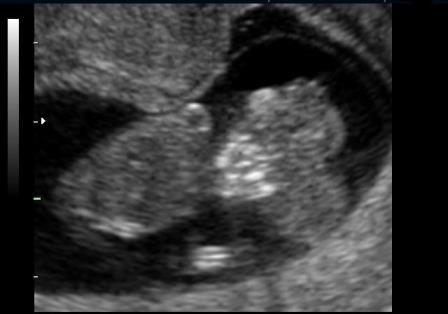

Nel I trimestre il processo distruttivo dell'encefalo non è ancora evidente per cui in questo periodo si osserva solo la mancata ossificazione delle ossa della volta cranica mentre gli emisferi cerebrali appaiono normali: si parla di acrania-exencefalia.

Alla fine del I trimestre il contatto dell'encefalo col liquido amniotico determina la distruzione del tessuto cerebrale con trasformazione dell'exencefalia in anencefalia.

La diagnosi ecografica è relativamente semplice. A 11-12 settimane la volta cranica è assente mentre gli emisferi cerebrali sono ancora riconoscibili e circondati da una sottile membrana a diretto contatto con il liquido amniotico ( acrania-exencefalia ). In sezione coronale l'estremo cefalico assume un aspetto "a mickey mouse"determinato dalla visualizzazione degli emisferi cerebrali come due strutture semicircolari al disopra delle orbite.